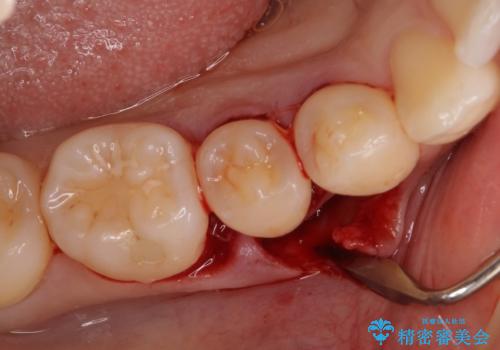

患者様は、他院で右下の歯を抜歯かもと言われました。全体の歯周病はなく、右下の1歯だけ骨が極端に減少していました(初診時歯周ポケット7mm。通常は3mm以下。)。その歯だけ咬合が強いことが原因と考えられたため、咬合を弱くする処置と減少した骨を再生する処置が必要になりました。

骨の再生治療手術をして10か月経過観察をしたのち、骨を平坦化する手術を行い、治療終了となりました。